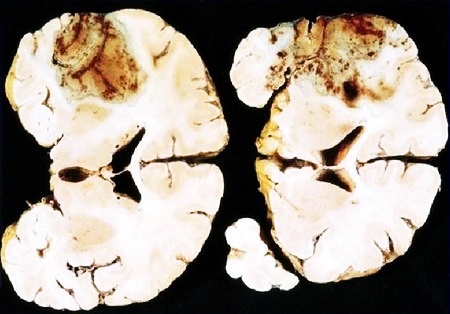

Ишемический инсульт может спровоцировать отек мозга, некроз задней и средней части мозгового ствола, вызвать вторичное кровоизлияние в мозговые отделы, что, в свою очередь, станет причиной летального исхода.

- Площадь и место расположения очага некроза. Если он находится в области жизненно важных центров мозга и поражает большое количество тканей, вероятность неблагоприятного исхода (вплоть до смерти) сильно возрастает.

Если были затронуты сразу несколько отделов головного органа, может наступить мозговая кома. Это наиболее тяжелый вариант течения инсульта, который сопровождается обширным некрозом мягких тканей. Кома часто сопровождается утратой способности к самостоятельному дыханию (регулярной одышкой) и полным нарушением работы сердечно-сосудистой системы. Риск летального исхода после перенесенной комы очень высок, а при благоприятном исходе шанс восстановить прежние функции организма составляет менее 15%.

Около 40 % летальных исходов, происходящих в первые три дня, связаны с обширным некрозом тканей мозга. Среди пациентов, переживших заболевание, около 70 % становятся нетрудоспособными инвалидами по причине неврологических расстройств. С течением времени эти нарушения угасают, благодаря чему через шесть месяцев после реабилитации расстройства остаются у 40% больных, а через год – у 25%.